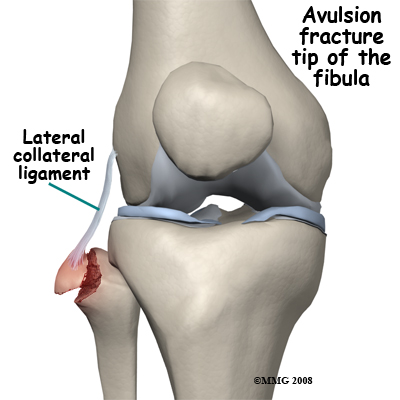

Avulsion fractures are common and easily missed. This may involve the lateral epicondyle, a Segond capsular avulsion or occasionally there is a tell tale avulsion of the tip of the fibular head indicating distraction of the lateral ligaments, this is termed the "Arcuate sign".

Fibular Collateral Ligament

• Lateral collateral ligament